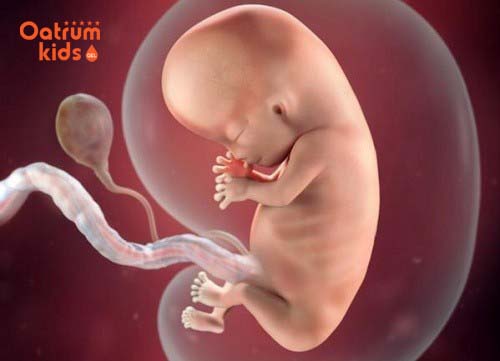

Các mẹ nên biết ở tháng thứ 2 trong tam cá nguyệt thứ nhất em bé đã dài khoảng 2,5cm, kích thước của bé lúc này như một quả nho Mỹ và có cân nặng vài gram.

Tuy nhiên về cơ bản hình hài của con cũng đã được phát triển đầy đủ. Cụ thể lúc này bé sẽ có một số thay đổi nhất định như:

- Phần đuôi của phôi thai lúc này đã hoàn toàn biến mất giúp bé có một hình dáng hoàn toàn như lúc bé được sinh ra.

Thai 8 tuần tuổi đã có mất đuôi và có đầy đủ các bộ phận.

- Các cơ quan nội tạng trong cơ thể lẫn cơ bắp cũng như hệ thần kinh đã định hình.

- Bé đã mọc mí mắt, mặc dù mí mắt này còn mờ và che mắt nhưng cũng có chút màu sắc

- Tim thai đã hoàn thành xong công việc phân chia thành bốn ngăn, đồng thời các van tim cũng bắt đầu hình thành.

- Giai đoạn này bé đã có miệng, mũi, có lỗ mũi và có dái tai nhỏ được định hình.

- Thai 8 tuần tuổi là lúc mà tay của bé đã có thể tự co lại được và hay đặt ở vị trí gần tim.

- Đồng thời lúc này bé đã xuất hiện khớp gối, hình thành đủ các chi nhưng cần phải những tháng tiếp theo mới có thể hoàn thiện tốt.

- Cơ quan sinh dục ở tuần thứ 8 cũng đã xuất hiện nhưng vẫn chưa rõ ràng nên chưa thể phân biệt được giới tính bé là bé trai hay gái được khi siêu âm.

- Lúc này về hình dáng chung đầu của con vẫn to hơn so với phần còn lại của cơ thể, tuy nhiên phần cổ và các xương trên khuôn mặt cũng đã hình thành.

- Cũng ở giai đoạn này nhau thai đã phát triển rất đầy đủ giúp sản sinh hormone để nuôi dưỡng thai nhi, giúp bé tăng cân nhanh chóng và phát triển.

Như vậy nhìn chung thai 8 tuần tuổi là cơ bản bé đã hình thành như một em bé thực thụ, có hình dáng và các bộ phận, tim đập.